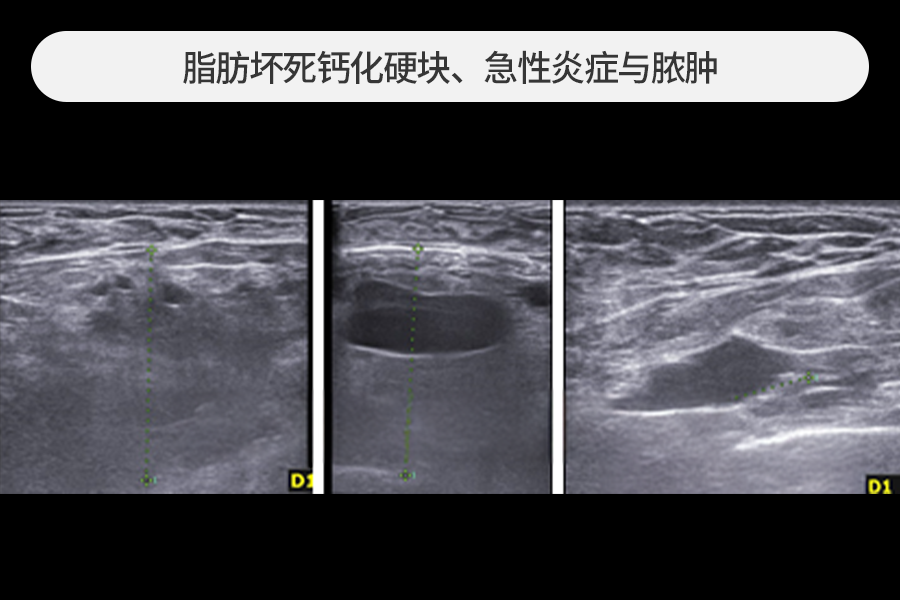

这是胸部脂肪移植后

因急性炎症导致脓液穿透

皮肤向外流出的状态。

去除了引发炎症的脂肪坏死硬块、

血肿及受损组织,并进行了急性炎症治疗。

这是胸部脂肪移植后因急性炎症导致脓液穿透皮肤向外流出的状态。

去除了引发炎症的脂肪坏死硬块、血肿及受损组织,并进行了急性炎症治疗。